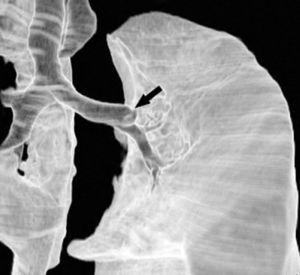

Pese a las conocidas limitaciones de la TC, ésta continúa siendo la técnica de elección en la estadificación del tumor en los pacientes con CPNM; su sensibilidad y especificidad en la determinación de la infiltración de pared oscilan entre el 38 y el 87% y del 40 al 90%, respectivamente, según las series. El desarrollo de nuevos equipos de TC helicoidal y principalmente las TC multidetectoras (TCMD) proporcionan unas imágenes 2D de mayor resolución con la posibilidad de hacer reconstrucciones multiplanares (MPR) en distintos planos del espacio e incluso 3D con la consiguiente mejora de la valoración del tumor, su extensión e infiltración de estructuras vecinas5 (fig. 4). Así, con la TCMD se puede poner de manifiesto con mayor fiabilidad la invasión de la cisura, la pared torácica o el mediastino, y además es capaz de determinar, gracias a las reconstrucciones de volumen, la relación exacta del tumor con la vía aérea (fig. 5). El progreso en la capacidad diagnóstica deriva del incremento en la resolución de las imágenes obtenidas y de la posibilidad de emplear nuevas aplicaciones como la broncoscopia virtual y la visualización en tiempo real. La broncoscopia virtual es útil para valorar la invasión del árbol traqueobronquial con la finalidad de planificar la cirugía, también como guía para el fibrobroncoscopista y, por último, porque permite ver el árbol bronquial distal a la estenosis (fig. 6)6. La capacidad de ver la imagen en tiempo real es especialmente útil cuando se emplea como guía en maniobras intervencionistas como biopsias percutáneas, ya sea con finalidad diagnóstica o como parte de la estadificación (fig. 7). Esta técnica de guía de biopsia denominada TC fluoroscopia reduce el número de pases y el tiempo global de la exploración, implica un menor riesgo de lesión de estructuras y permite la visualización inmediata de las posibles complicaciones7.